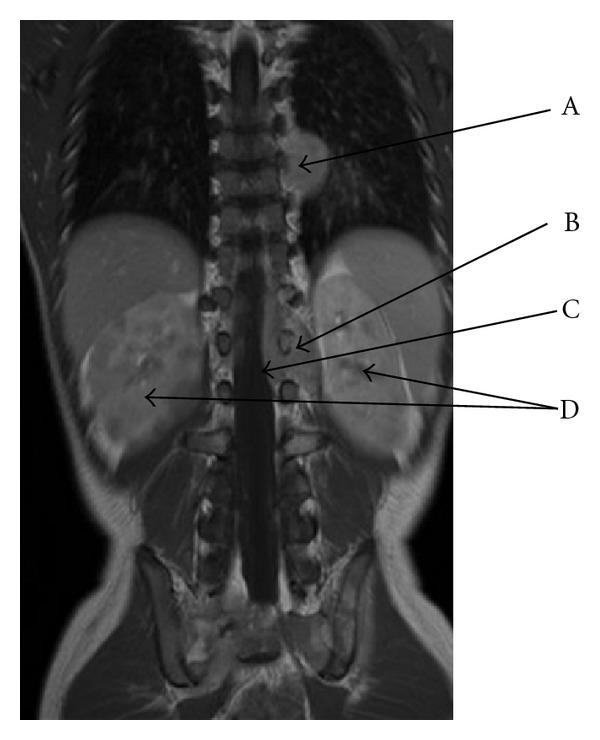

Paravertebral malignant tumors constitute 4.8% of cancer cases in pediatric oncology and are mostly composed of neuroblastoma (46.4%) and soft tissue sarcomas (35.7%). We describe the case of a Caucasian 6-year-old boy who was admitted for middle back pain radiated to limbs and progressively increasing weakness of the legs, suggesting a spinal cord disease. The exploration revealed two paravertebral masses extending through the neural foraminae into the epidural space. The association with elevated serum neuron specific enolase suggested at first the diagnosis of neuroblastoma, but the pathological examination revealed a Burkitt's lymphoma. This is a rare location of sporadic Burkitt's lymphoma with neurologic syndrome as first symptoms.

椎旁恶性肿瘤占小儿肿瘤病例的4.8%,主要由神经母细胞瘤(46.4%)和软组织肉瘤(35.7%)组成。我们描述了一名6岁白人男孩的病例,他因中背部疼痛放射至四肢且腿部无力逐渐加重而入院,提示脊髓疾病。检查发现两个椎旁肿块通过神经孔延伸至硬膜外间隙。血清神经元特异性烯醇化酶升高起初提示神经母细胞瘤诊断,但病理检查显示为伯基特淋巴瘤。这是散发性伯基特淋巴瘤罕见的发病部位,以神经综合征为首发症状。